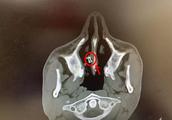

Arrive from art hind now in the time of 1 this many months, ms. Chen says to be in everyday suffer. And besides ache, the nose that she discovers herself actually pervious to light, be in lamplight or it is sun's rays falls, body of paragraphs of whole Peng is pervious to light. Ms. Chen expresses, this kind of case should not appear, because the Peng body material of own choice is nonexistent pervious to light problem, use silica gel to just can have pervious to light feeling commonly.

Ms. Chen considers as the ache after the error of the hospital brings about her art, bridge of the nose is pervious to light. And the hospital expresses: "Now ability operation a month, aching feeling is a convalescence only, 3 months after art and half an year come again further consultation with a doctor. " later the comparative figure after the art before taking out Ms. Chen skill, state the operation is very successful, do not have pervious to light problem, it is strut only. Nevertheless, the friend of Ms. Chen refutes the nose that says he is to use silica gel stuff on the spot, the operation still is after Ms. Chen, do not have pervious to light circumstance.